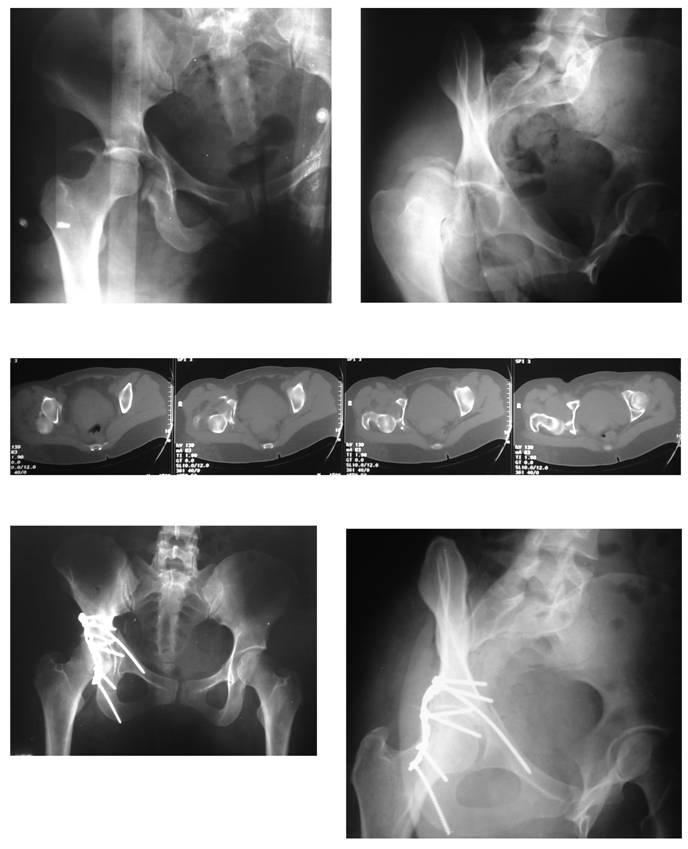

Figure 2

Pre-operative radiographs and CT scan, and postoperative radiographs of a patient (57 y/o male, road-traffic accident, unrestrained) without fixation of the anterior component of the transverse acetabular fracture with. Observe the anatomic reduction of both column of the acetabulum and the perfect congruency between the femoral head and the roof. Follow-up duration of 26 months.